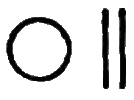

Symp. Each febrile paroxysm is of three periods or stages—the cold, the hot, and the sweating stage, and these occur in regular succession. The cold stage commences with great languor and aversion to motion; a sense of coldness down the back soon follows; then the extremities become cold, the fingers shrunken, and the nails blue; the skin assumes that peculiar condition which is commonly known as ‘goose-skin,’ the patient shivers, his teeth chatter, and he is glad to draw close to the fire or envelop himself in blankets. After this state of things has continued for a greater or less time, the heat of the surface begins to return, the patient has flushings and becomes warmer and warmer, and ultimately the whole surface is of a dry burning heat; intense thirst, restlessness, severe headache, and sometimes delirium, characterise this second or hot stage. After this stage has continued for some time, another change comes over the patient; moisture appears on the face and forehead, the harsh and hot skin becomes soft, and at last a copious sweat breaks out over the whole surface. This is the third or sweating stage, and after it has passed, the several functions of the system return to their ordinary condition. The paroxysm may return daily (QUOTIDIAN AGUE); or every other day (TERTIAN A.); or every fourth day, including that of the first attack (QUARTAN A.).